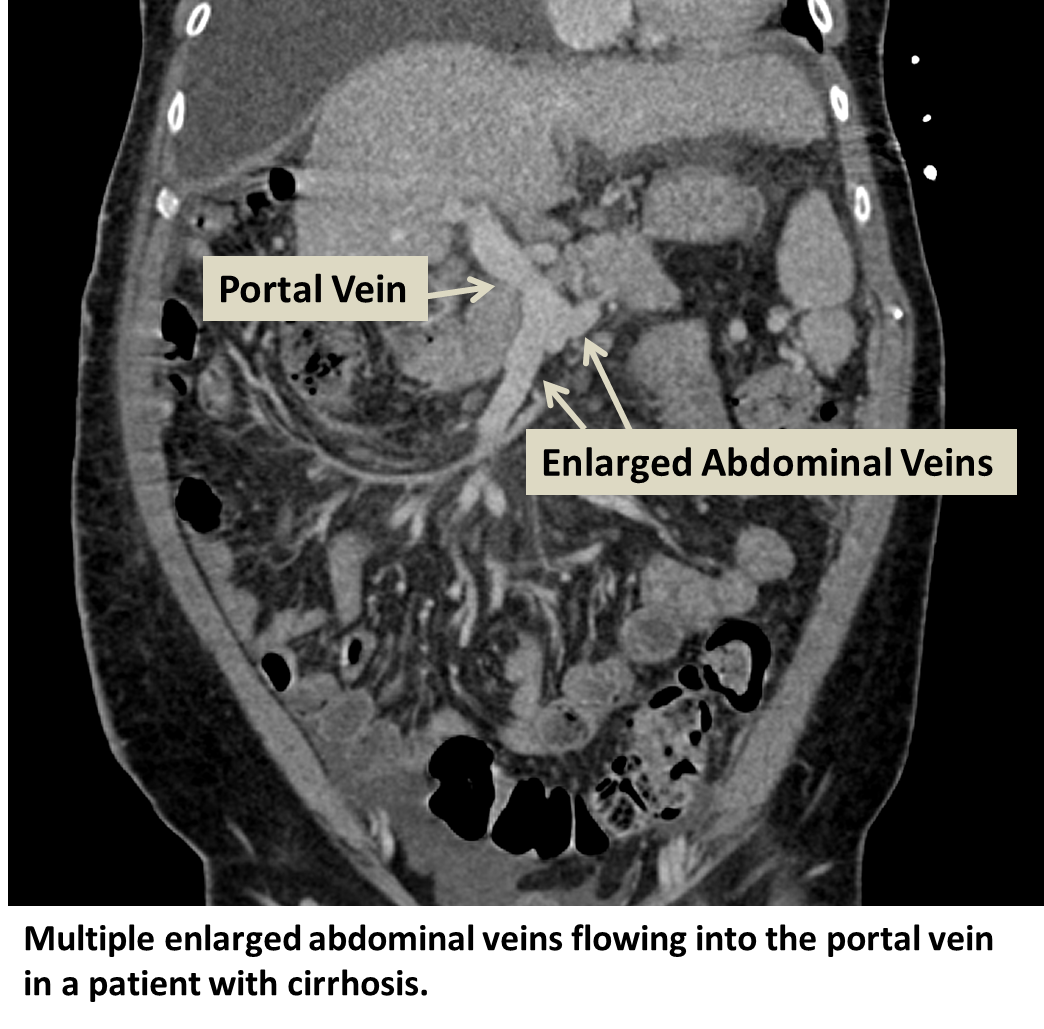

Abdominal CT And MRI Findings Of Portal Hypertension In Children And

Portal Hypertension Symptoms Diagnosis And Treatment